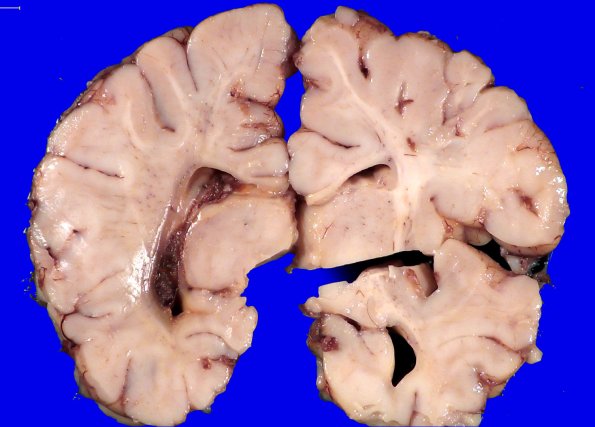

Washington University Experience | VASCULAR | Hemorrhage - Neonatal | 29A1 IVH (Case 29) Gross 1

29A1,2 At autopsy an intraventricular hemorrhage was found centered on the left choroid plexus with diffuse ventricular staining that appeared consistent with an age of nearly two months. The white matter is involved by diffuse hypoxic-ischemic insult.